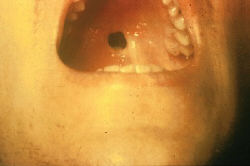

3. The following are associated with the sign shown above:

a.

b.

c.

d.

e.